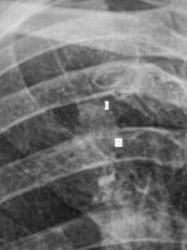

Иллюстрации 3, 4. Фрагменты изображения, полученного на CR – системе. Гомогенизация тени правого корня в области тела, измерены размеры «очагового образования» - 8 х 15 мм.